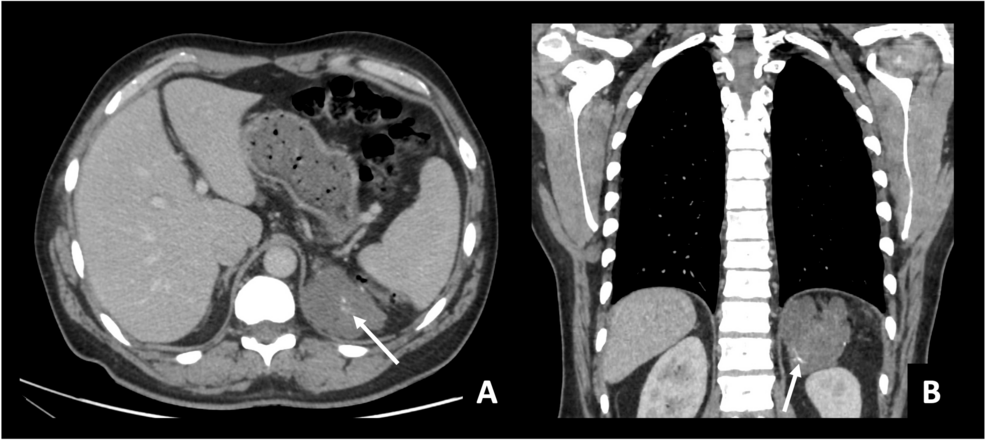

يُعد الرنين المغناطيسي أهم فحص للكشف عن الأورام خلف العمود الفقري.

أهمية MRI أنه:

-

يُظهر الورم بدقة

يحدد حجمه وموقعه

يوضح مدى تأثيره على الفقرات والأعصاب

يساعد على التخطيط للعلاج الصحيح